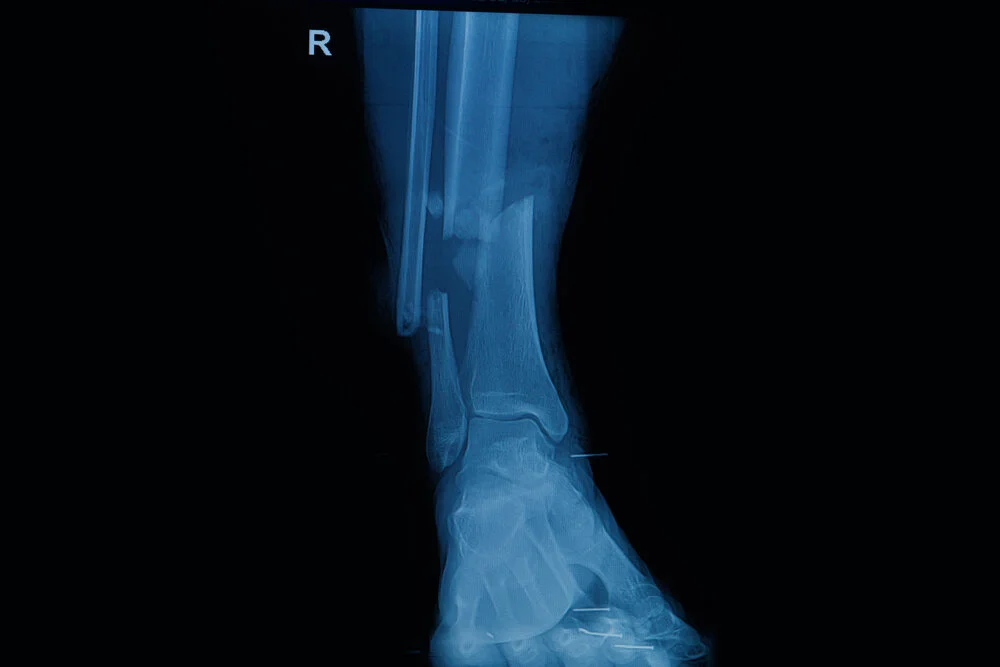

Have you ever broken a bone? We hope you haven't, but it’s a common injury that happens to people every day! Any break in the structure of a bone is known as a ‘fracture’. We’ve written a quick guide to understanding all the lingo relating to fractures below. Let’s check it out!

Types of fracture: General description

Fractures are broadly classified into two main types:

•          Closed: The bone fractures and the overlying skin remains intact.

•          Open: The bone fractures and protrudes through the skin exposing the bone and other tissues to the elements. These types of fractures are prone to becoming infected, which complicates everything.

Types of fracture: Now let’s REALLY break it down!

Each fracture can also be given a more specific description based on where exactly the bone is broken and in what way it has broken:

•          Comminuted: The bone is broken into more than two pieces, possibly into several fragments